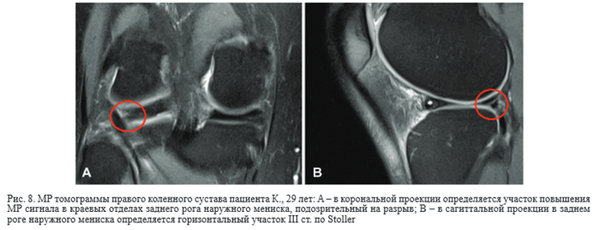

Сухожилие подколенной мышцы – основная структура заднелатерального комплекса, располагающаяся интраартикулярно, экстрасиновиально, поэтому его ход повторяет одноименное синовиальное влагалище, жидкостные участки в котором ошибочно могут быть расценены во фронтальной и сагиттальной плоскостях как краевой разрыв наружного мениска. Однако использование всех стандартных и прицельных косых срезов позволяет избежать данной диагностической ошибки [20, 21] (рис. 7)

Напротив,краевой разрыв имеет нечеткий и неровный контур, а на уточняющих кадрах определяются до - полнительные патологические линии (рис. 8).